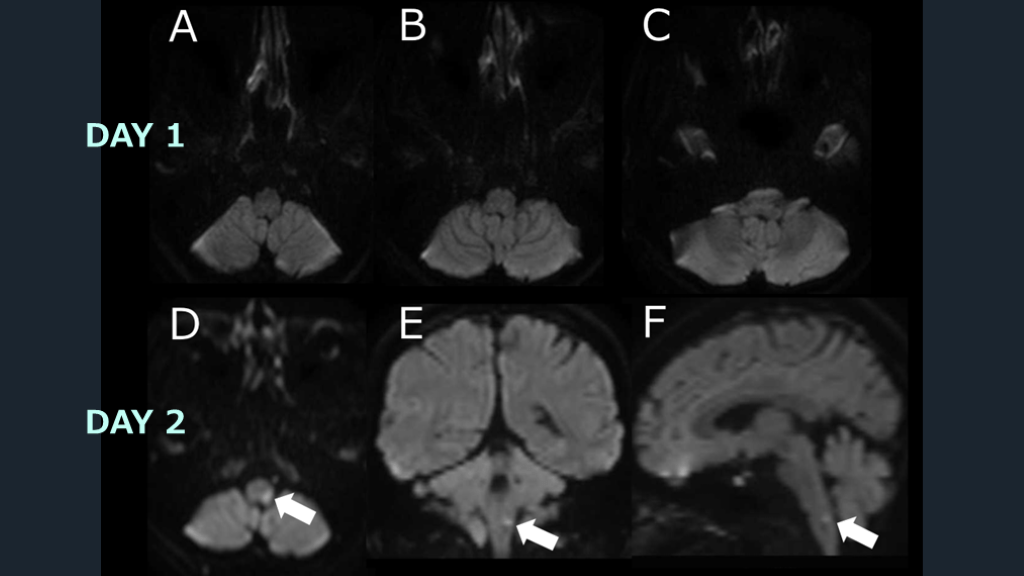

MRIの偽陰性を 克服するために① 後者に関しては、MRI検査は結果が偽陰性の可能性がありうる、という前提で診療を進めていく必要がある。そして、DWI偽陰性は2つの要因で起こりうることを押さえておく。1つは、MRI施行が発症早期の場合に起こりうる「時間的偽陰性」の要因である。もう1つは後方循環系脳梗塞で起こりうる「部位的偽陰性」の要因である。そして脳幹部梗塞ではこの部位的偽陰性が多いことが知られている。時間的偽陰性を克服するためには、「入院後に時間を空けて2回目のMRIを再検すること」で克服可能である。

MRIの偽陰性を 克服するために② 部位的偽陰性を克服するためには、「DWIの2方向(水平断に加えて冠状断を追加)の撮像」で克服可能である。撮像方向を加えることで見落としを減らすことが出来る。以上より、現実的な対応は次の如くとなる。通常のプロトコールの撮像で初回MRI検査におけるDWIが陰性だったとする。その場合、「入院翌日に、DWIを2方向で再度撮像する」ことで、時間的・空間的偽陰性を排除することが可能になる。MRIを診断の切り札として行う脳梗塞診療の偽陰性によるピットフォールも慎重に意識することで、脳梗塞診断は不安を減らすことが出来る。

DAY 1 DAY 2

脳梗塞を診断するためのDWIの感度は92%、特異度は75%とされる10)。DWIは発症後1時間以内の脳梗塞を特定できる。ただし、脳梗塞の約7%は DWIで陰性になりうる11)。DWI陰性の脳梗塞患者は先述のごとく、脳幹部梗塞で多く報告される。例えばMLF症候群や片麻痺症状を呈するラクナ梗塞の場合によく経験される。後方循環障害による脳梗塞患者は、前方循環障害の脳梗塞患者よりも DWIが陰性となる可能性が5倍高くなる。最初のDWIが陰性だった脳梗塞疑いの患者の約3分の1が、2回目のスキャンで高信号に変化した、という報告もある10)。 DWIは信じられない? Eur J Radiol Open. 2023 Nov 4:11:100533.

先述の如く、脳幹部梗塞疑いの場合には1度のMRI検査でも脳梗塞は否定しきれない、という意識は重要である。症候的に脳幹部梗塞の可能性が示唆されるにも関わらずDWI陰性だった場合には、2度目のMRI撮影を行うというアクションが重要である。 この場合には脳梗塞に準じて入院対応とし、2回目のMRI検査を行う。時間的・部位的偽陰性を克服するための「2回目のDWIによる2方向撮像」を活用し、診断を明らかにしていく。 DWIの偽陰性を克服する。